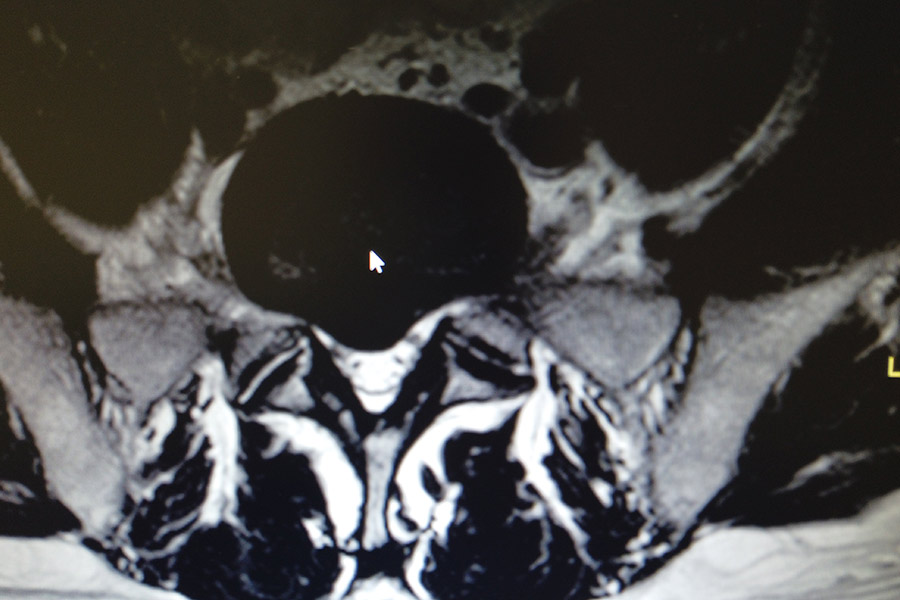

Caso clínico: endoscopia de columna multinivel L4L5 y L5S1

Los síntomas que presentaba el paciente eran dolores acentuados en las piernas, claudicación a la marcha y calambres y hormigueos en las piernas.

Durante la intervención quirúrgica, se abordarán los dos niveles mediante la técnica de endoscopia de columna.